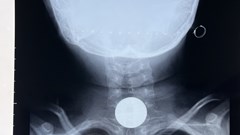

VHO - Vừa qua, giải pháp VinDr-Mammo do VinBigdata (thuộc Tập đoàn Vingroup) phát triển trở thành sản phẩm đầu tiên và duy nhất tại Việt Nam được Cục quản lý Thực phẩm và Dược phẩm Hoa Kỳ (FDA) cấp chứng nhận trong lĩnh vực hỗ trợ chẩn đoán ung thư vú, chính thức gia nhập vào thị trường khó tính nhất thế giới.